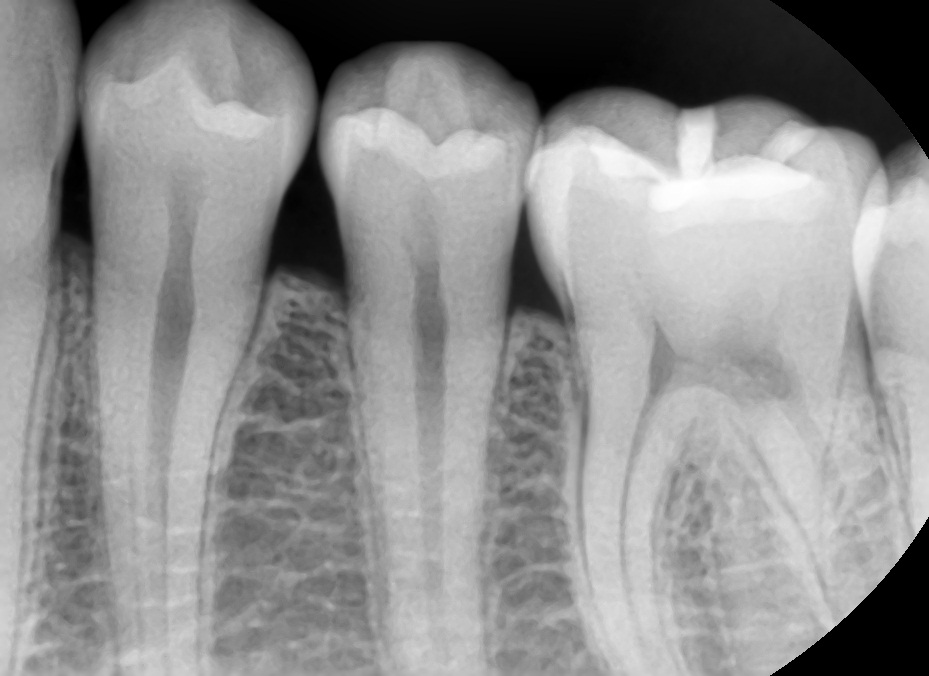

상기된 사진과 같은 치아상태에서 의사선생님이 국소적 법랑질우식이있으나 지켜보자했습니다. 헌데 요즘 게을러져서 한달 반정도를 4일에한번주기로 꼼꼼하게양치하고 치실질하는 식으로 했었는데요, 이것이 충치를 한달 반동안에 신경치료해야할만큼 위험하게 번질수도있나요?

21세 남성이고 3년간 안닦았다가 법랑질에 우식생긴이력이 있는지라 좀 우려스럽습니다

사진에서 보기에는 범랑질 표면에 살짝 표면충치가 생긴 것으로 보입니다. 범랑질 표면에 생긴 충치가 한달반 만에 상아질로 까지 진행될 가능성은 희박합니다.

충치가 교합면에도 잇고 치아 사이에도 충치가 잇는거 같습니다. 치료를 받으셔야될것같습니다.